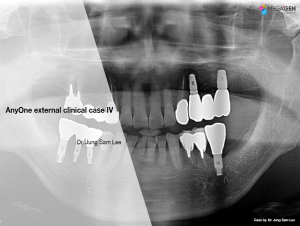

Keywords

e.g. product name, treatment solution, author, clinician name